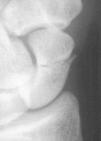

Son aquellas que no varían la forma y el volumen del escafoides, manteniendo su geometría espacial. Son fracturas que aparecen incompletas, precisando tratamiento mínimo y normalmente tienen una consolidación rápida. Este grupo representa sólo el 8% de las fracturas del escafoides14 y comprende los siguientes tipos de fracturas: a) fracturas del tubérculo (Fig. 1), en las que no siempre es necesaria la reducción o inmovilización, y b) fracturas incompletas del cuerpo del escafoides (Fig. 2): el diagnóstico de las mismas puede ser difícil, pudiendo pasar inadvertida. Es importante realizar controles radiológicos periódicos durante el proceso de consolidación para descartar que en realidad se trate de una fractura inestable.

Figura 2. A y B: Fractura incompleta del cuerpo del escafoides. En ocasiones puede ser difícil su diagnóstico radiológico, siendo necesario repetir la exploración radiológica a los 10 días del accidente o utilizar proyecciones especiales.